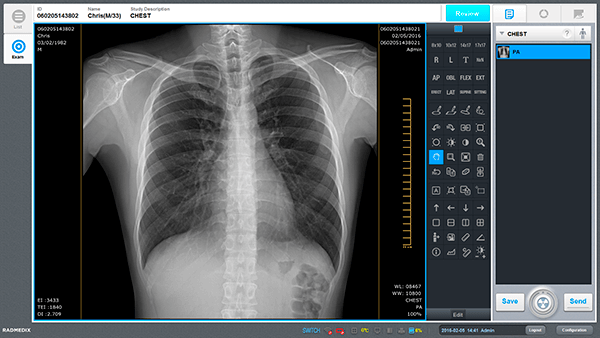

Software de adquisición de imágenes para radiología general

Desarrollada por tecnología avanzada de procesamiento de imágenes y una interfaz fácil de usar

Funciones versátiles de edición de imágenes

- Disfruta de la costura automática (hasta 4 imágenes), el etiquetado automático y la función de recorte automático con Econsole.

- Herramienta de control de imagen versátil para comodidad del usuario.

- 9 opciones de parámetros de imagen basadas en la preferencia de imagen.

- Barra de herramientas personalizable.